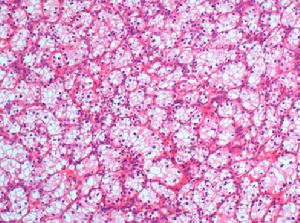

发病机制:肾盂癌绝大多数为移行细胞癌可分为4级健康搜索。Ⅰ级:乳头状伴正常黏膜;Ⅱ级:乳头状伴少量多形性变和核分裂;Ⅲ级:扁平移行细胞伴显著多形性变和核分裂;Ⅳ级:极度多形性变因肾盂壁薄易发生淋巴或血行转移预后不良。 医学百科网 | YxBaike.Com

鳞状细胞癌约占肾盂癌的15%,病变扁平,质硬迅速浸润达肾脏周围肾门及区域淋巴结确诊时多已转移预后差。腺癌极为少见。肾盂肿瘤可发生于肾盂的任何部位有多中心发生的特点可同时或先后发生输尿管肿瘤或膀胱肿瘤在乳头状瘤或乳头状癌患者中较为多见,而在平坦的浸润性乳头状癌患者中较为少见。关于肾盂肿瘤的多发现象,目前有4种解释:①淋巴途径扩散;②经黏膜直接扩散;③多中心病灶;④肿瘤细胞脱落种植在输尿管或膀胱黏膜上,继续生长而成。 医学百科网 | YxBaike.Com